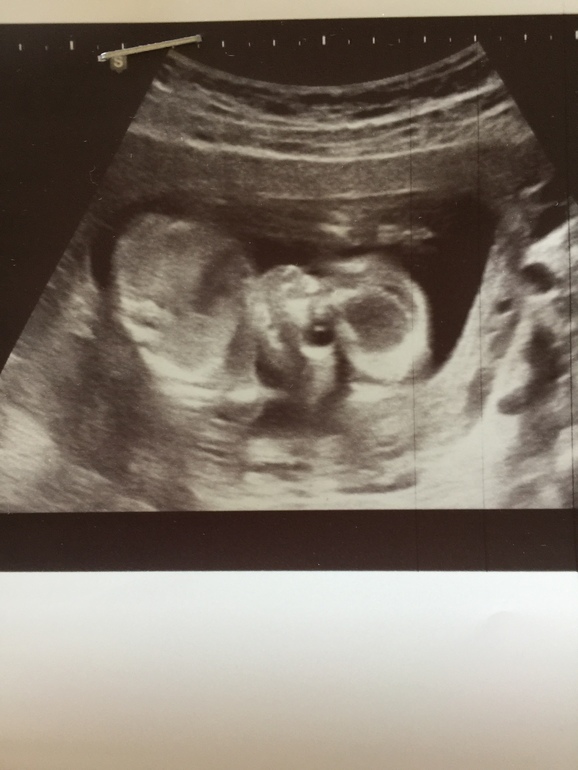

Похоже,мы знаем пол:)

И мы со всех сторон рассматривали-рассматривали--------иииииии---- девочка пока👧🏼

Такие глазищи!!!!ручками закрывается,машет,стесняшечка:)

Все у ребеночка в норме,ттт👌👌👌

Лежим уже головкой вниз